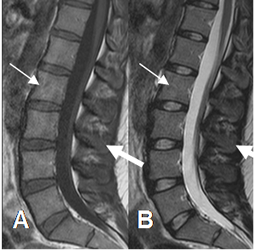

Fig 3. Medula ósea roja normal.

A: RM sagital en T1 y B: RM sagital en T2. Medula con señal intermedia en ambas secuencias (Flechas delgadas), mas alta que el músculo. (Flechas gruesas).